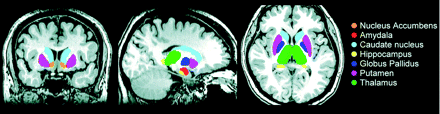

Volume estimation for 7 bilateral DGM structures, including the nucleus accumbens, amygdala, caudate, hippocampus, pallidum, putamen, and thalamus, was performed by using FIRST, Version 1.2 (FMRIB's Integrated Registration and Segmentation Tool http://www.fmrib.ox.ac.uk/fsl/first/index.html) which is part of FSL Version 4.1.5 (FMRIB Software Library).22 FIRST, a probabilistic adaptation of the active appearance model,23 is a completely automatic segmentation and registration tool for DGM. The shape and appearance model of each DGM structure used in FIRST is constructed from manually segmented images of 336 subjects provided by the Center for Morphometric Analysis, Massachusetts General Hospital, Boston. The manual labels are parameterized as surface meshes by a deformable surface and modeled as a point distribution function. Using a set of fixed triangles, each DGM surface mesh was reconstructed. The apex of the adjoining triangles is called a vertex. To fit the shape and appearance model to each participant's T1 image and to perform DGM tissue segmentation, we used a robust DGM structure alignment consisting of a 2-stage linear registration. The first stage is a standard whole-brain 12-df affine registration to the MNI152 template. The second stage of DGM registration applies 12-df registration by using the MNI152 subcortical mask to include voxels within the DGM regions. After registration, boundary correction and mode selection with default settings were used to determine each of the final DGM segments. These segments were projected back into individual native spaces by inverse transformation matrices from the initial registration procedures, and the absolute DGM volumes were calculated (Fig 1). An expert radiologist verified the accuracy of each participant's native space DGM segments, and no errors were identified.

FIRST segmentation of the subcortical nuclei in a patient with liver cirrhosis. Volume estimation for 7 bilateral subcortical nuclei, including the nucleus accumbens, amygdala, caudate, hippocampus, pallidum, putamen, and thalamus.